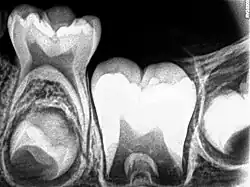

_showing_Deciduous(Milky_or_Primary)_Tooth_75_and_developing_crown_of_Permanent_or_Secondary_Teeth_35%252C_36_and_37.jpg)